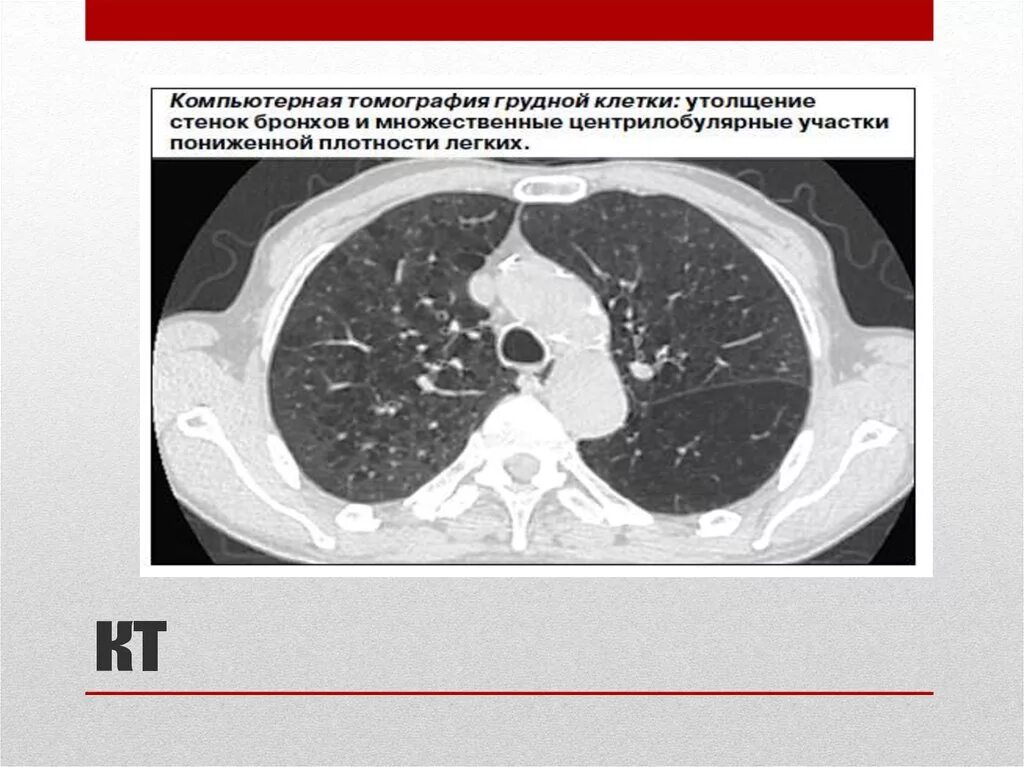

Утолщение бронха